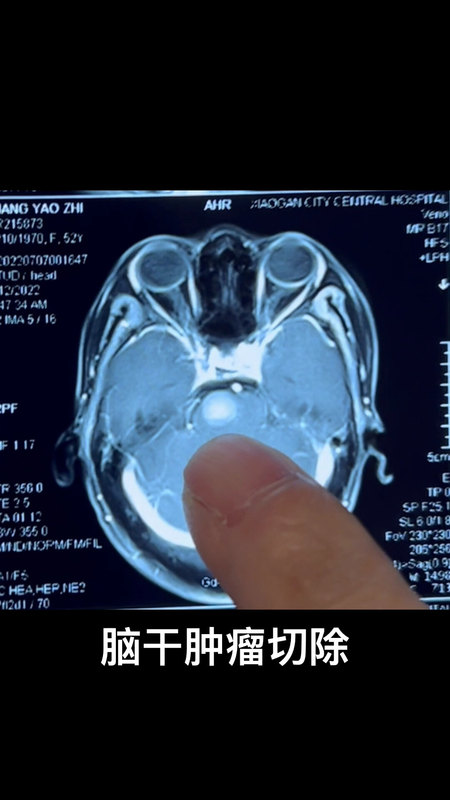

腦干腫瘤切除

符榮醫(yī)生的科普號2023年07月14日121